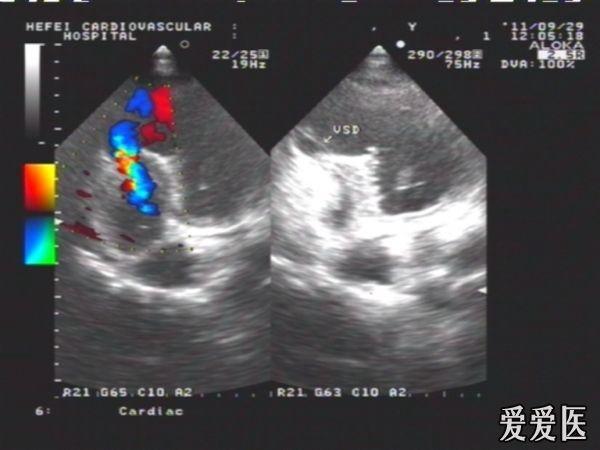

陈旧性前壁心梗继发肌部室间隔缺损典型病例

患者,女性,66岁,活动后心慌,胸闷2年,血压135/70mmHg,HR:78次/分。